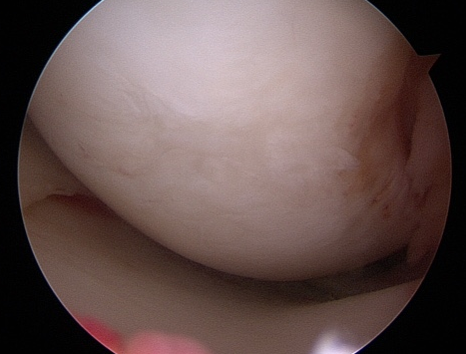

Filling of the Defect with BioCartilage

Intra-operative filling of defect with Biologic Cartilage

Second look showing healed defect